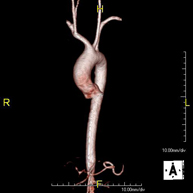

- Angio-RM Aorta Abdominal

Prueba diagnóstica no invasiva que consiste en el estudio de la arteria aorta abdominal, obteniendo imágenes de alta definición anatómica mediante el empleo de un campo electromagnético y ondas de radio (con un emisor y un receptor). Es indispensable el uso de contraste intravenoso paramagnético (gadolinio). Sin embargo, no utiliza radiación ionizante. La calidad de las imágenes permite realizar reconstrucciones en 2D y 3D. Está indicado en aquellos pacientes con enfermedad vascular (aterosclerosis), estudio de aneurismas, en estudios pre-quirúrgicos de lesiones adyacentes a la aorta abdominal como "mapa" vascular…